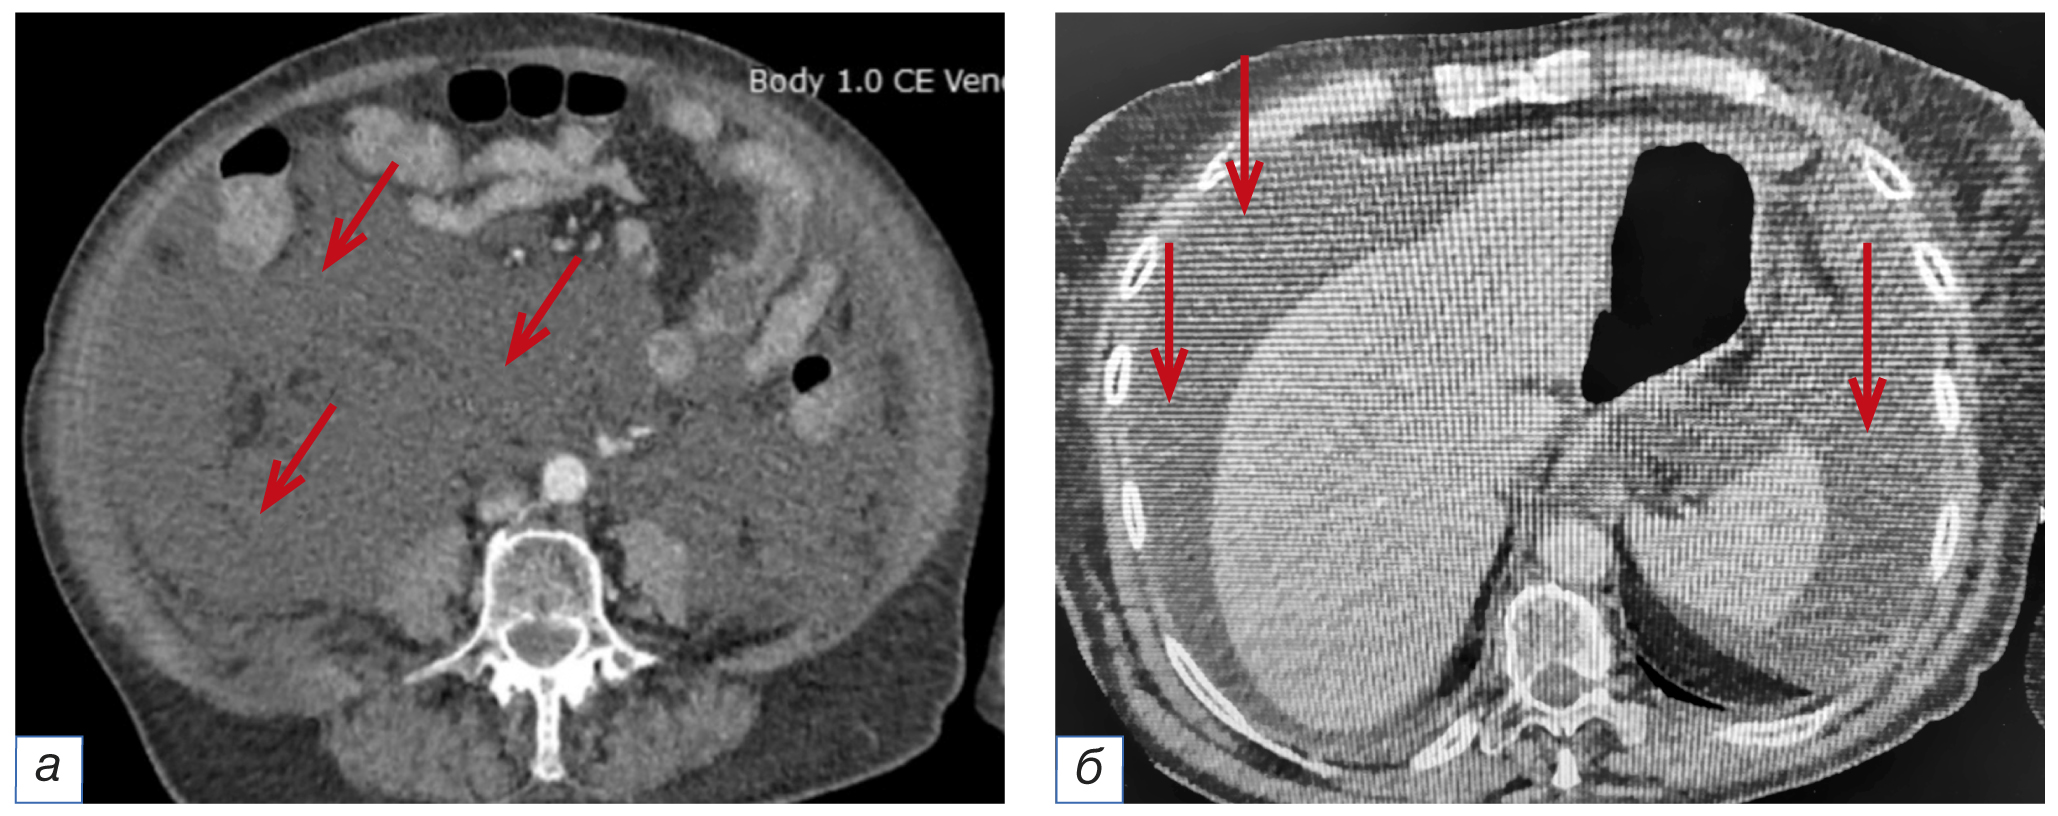

По завершении операции выполнен поворот пациентки на спину, отмечены значимое увеличение живота в объёме, тимпанический звук при перкуссии. После восстановления уровня сознания пациентка была экстубирована; предъявила жалобы на тянущие боли в области живота, позывы к мочеиспусканию, затруднение дыхания, в связи с чем направлена в отделение реанимации и интенсивной терапии (ОРИТ) для послеоперационного наблюдения и дообследования. По данным УЗИ органов брюшной полости выявлено наличие свободной жидкости. Компьютерная томография (КТ) органов брюшной полости показала наличие свободной жидкости в брюшной полости, отёк забрюшинного пространства и паранефральной клетчатки справа (рис. 4–6).

Рис. 5. Свободная жидкость в брюшной полости (стрелки на изображениях а, б) по данным компьютерной томографии.

Fig. 5. Free liquid in the abdominal cavity by computer tomography (marked with arrows).